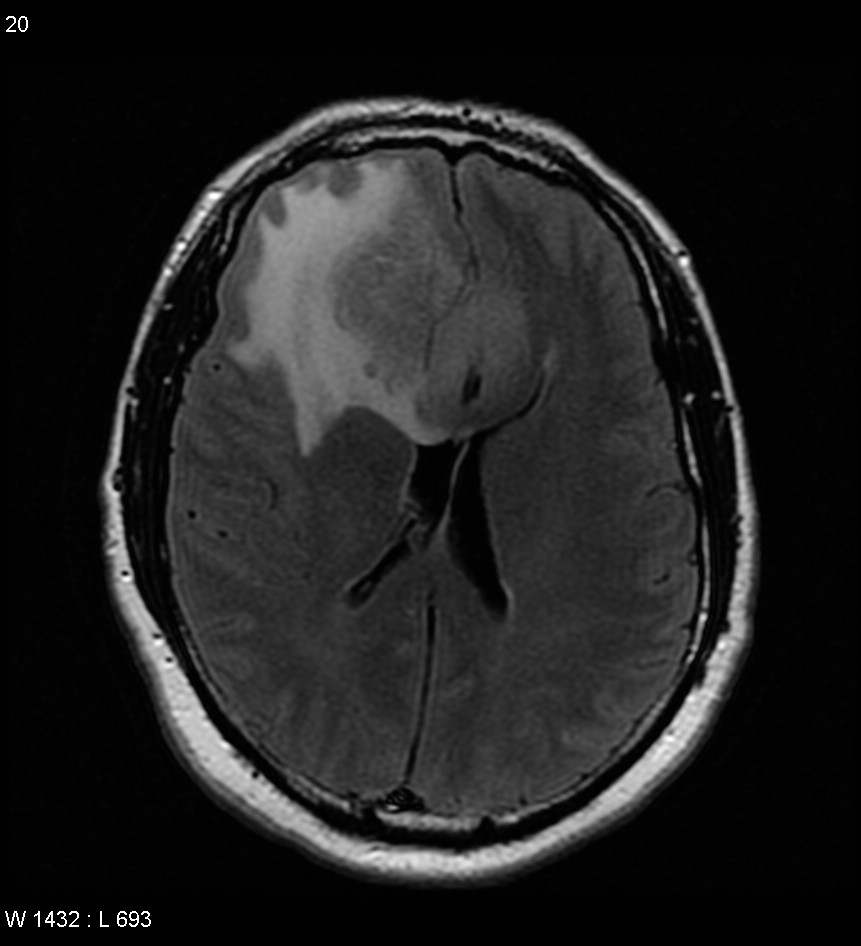

嗅沟脑膜瘤约占颅内脑膜瘤的1/10,是颅前窝肿瘤中较多见的一种。 肿瘤起自筛板部位的硬脑膜,多呈球形突向额叶底部,既可位于一侧,也可向两侧生长。主要接受来自筛前动脉及其分支脑膜前动脉的供血,大脑前动脉和大脑中动脉有时也有小分支参与。嗅沟脑膜瘤手术难度大吗?

及早手术。嗅沟脑膜瘤多可完全切除,一旦确诊,应争取及早手术。

嗅沟脑膜瘤切除一般不至于损伤重要结构。但肿瘤较大者,后较可能延至蝶骨嵴内侧和鞍上,因而在分离时,需注意勿损伤视神经、大脑前动脉、前交通动脉及其重要的穿通支。按脑膜瘤的处理原则,为全切肿瘤,以防复发。